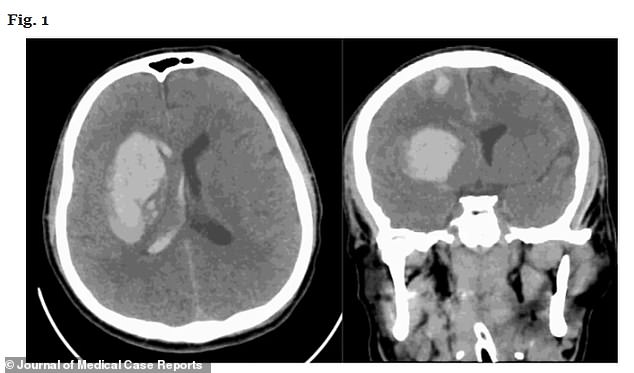

Scans revealed multiple brain bleeds and he underwent an emergency procedure where part of the skull is removed to relieve pressure.

Tests carried out after surgery to remove excess fluid from the brain on his 99th day in hospital showed he had a C. auris infection.